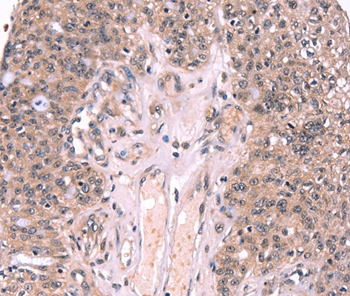

Immunohistochemical analysis of paraffin-embedded Human ovarian cancer tissue using #37561 at dilution 1/20.

Immunohistochemical analysis of paraffin-embedded Human prostate cancer tissue using #37561 at dilution 1/20.